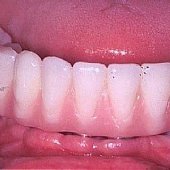

• Die fertige fest sitzende Brücke im Unterkiefer.

• Röntgendarstellung einer fest sitzenden Unterkieferbrücke mit 5 Implantaten.